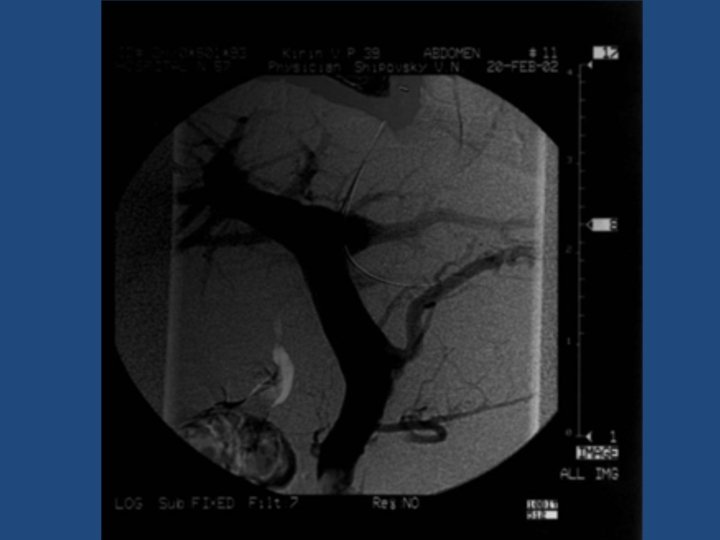

Результаты TIPS • • • Длительность процедуры 1 час до 3, 5 часов Повторные кровотечения – 10% Стеноз стента в течение двух лет – 20% Печеночная энцефалопатия Летальность 20% Максимальный срок наблюдения = 5 лет

Методика дистанционного обследования после TIPS • Клинический осмотр и лабораторные анализы • ЭГДС • Ультразвуковое дуплексное исследование портального кровотока • Ангиография ?